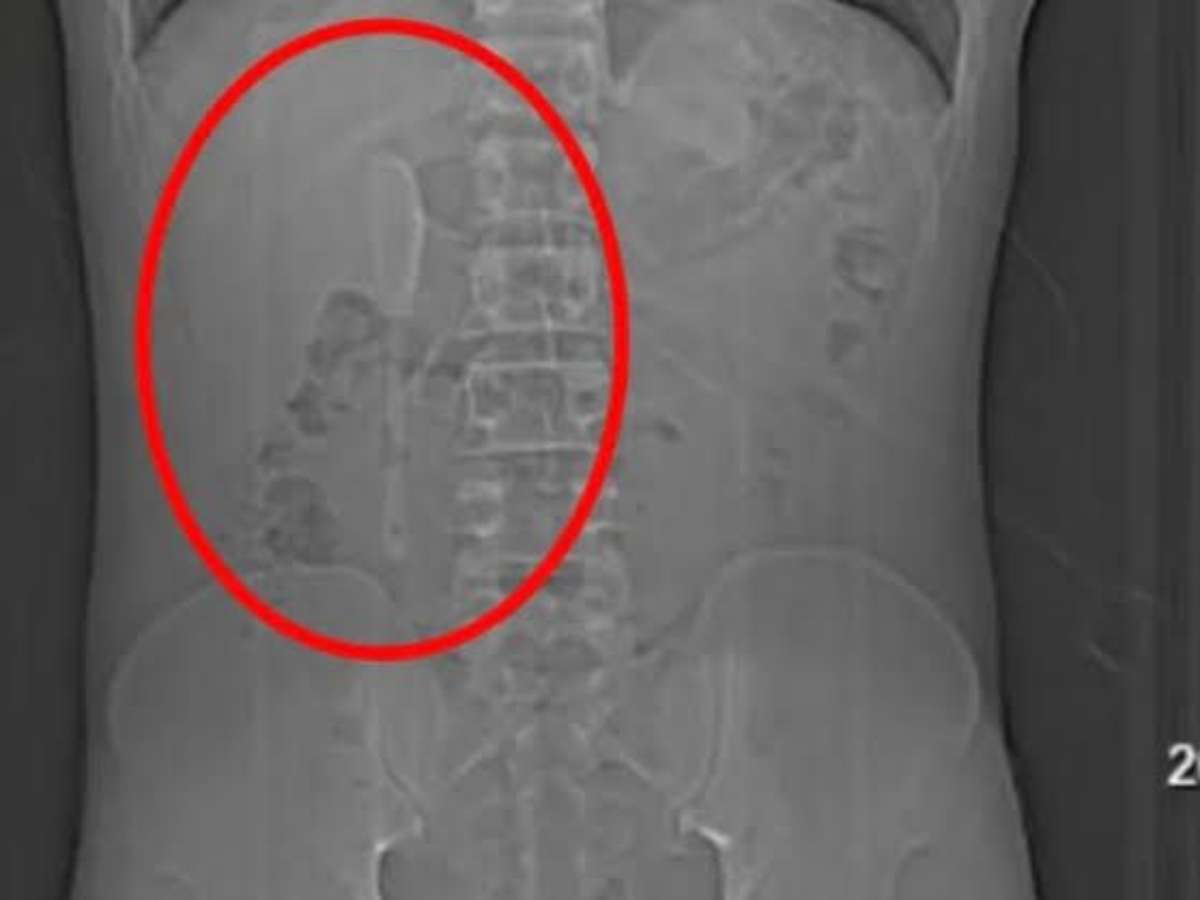

Yan continuou sua rotina normalmente e até praticou exercícios físicos sem apresentar sintomas graves durante os meses seguintes, mas em em junho, procurou um hospital em Xangai, onde exames revelaram a colher presa em uma posição delicada no duodeno.

A cirurgia endoscópica para retirar a colher durou cerca de nove horas e envolveu o uso combinado de dois tipos de pinças para puxar o utensílio de volta ao estômago e, em seguida, removê-la.

Os médicos explicaram que a extração seria difícil devido à superfície lisa da colher e à localização que colocava o intestino em risco de perfuração, podendo causar inflamação ou hemorragia intensa. Apesar do risco, a operação foi bem-sucedida.